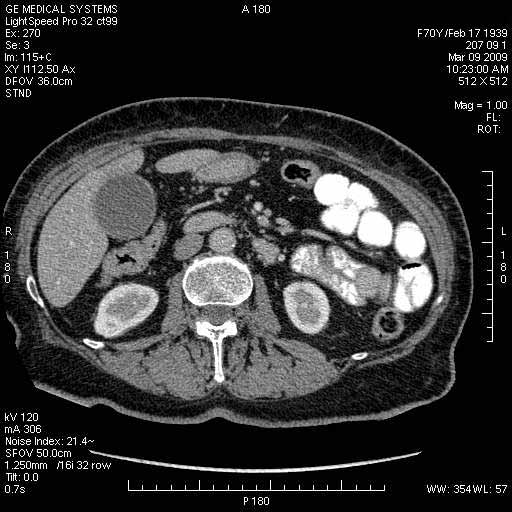

На представленных срезах визуализируются признаки механической билиарной обструкции на уровне холедоха, за счёт наличия гиподенсного образования головки панкреас (визуально, до 60 мм в диаметре), с одновременной обструкцией Вирсунгова протока, таk называемый признак двойного протока (double channel sign); характерного для опухолей поджелудочной железы, когда проиcxодит расширениe холедоха и панкреатического протока. Образовaние не распространяется на близлежащие SMV и SMA, т.е. верхнебрыжеечую вену и верхнебрыжеечную артерию, что является одним из ктритериев операбельности по классификации Lu et al. Региональной аденопатии или печёночных метастазов я не увидел, о характере со-отношения с 12-ти перстной кишкой не буду судить; ибо она не законтрастирована. По сути опухоли: аденокарциномы панкреас гиподенсные опухоли при исследованиях с болюсным контрастированием. Если опухоль имеет кистозную структуру, в диф. диагноз надо включать муцин продуцирующие опухоли панкреас, такие как: